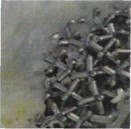

The implant surface is highly porous titanium, which allows initial stability and long-term bone integration (in-growth). This technology has been successful in clinical use around the world for more than 30 years in joint replacement surgery. The biocompatibility of the titanium implant allows the bone to grow inside the surface of the prosthesis, which makes the bone-implant structure one solid unit. This is known as osseointegration.

Bone Penetration

Images depicting bony in-growth

Immediate post-surgery

6 Weeks post-surgery